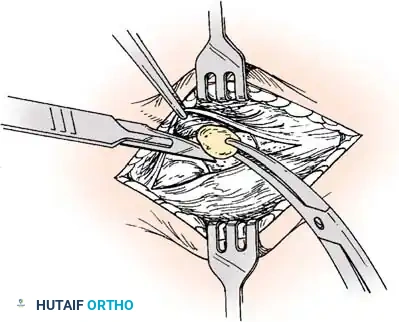

جراحة إزالة التحام العقب والزورقي

في حالة التحام العقب والزورقي، يعتبر الاستئصال الجراحي للجسر العظمي هو الخيار المفضل، خاصة لدى الأطفال والمراهقين الذين لا يعانون من خشونة في المفاصل.

يقوم الجراح بإزالة الجسر العظمي بالكامل لضمان عدم عودته. ولمنع تكوّن العظم مرة أخرى في نفس المكان، يتم وضع نسيج عازل في الفراغ الناتج، مثل جزء من عضلة مجاورة (Extensor digitorum brevis) أو نسيج دهني، أو استخدام الشمع الطبي. أثبتت الدراسات أن هذه الجراحة تنجح بنسبة عالية في تخفيف الألم واستعادة جزء كبير من حركة المفصل.